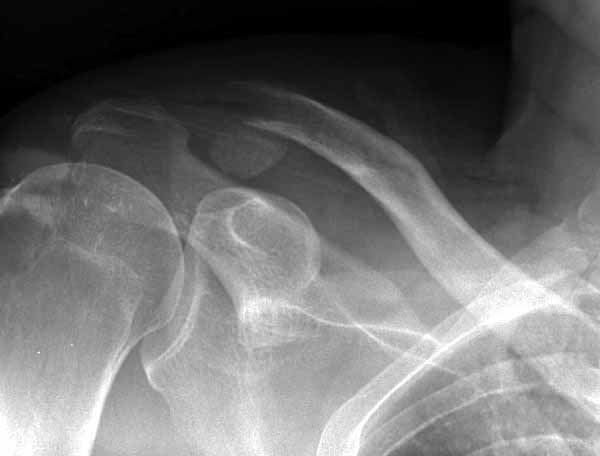

img050.jpg

137KB (140680 bytes)

1.JPG

60KB (62415 bytes)

|